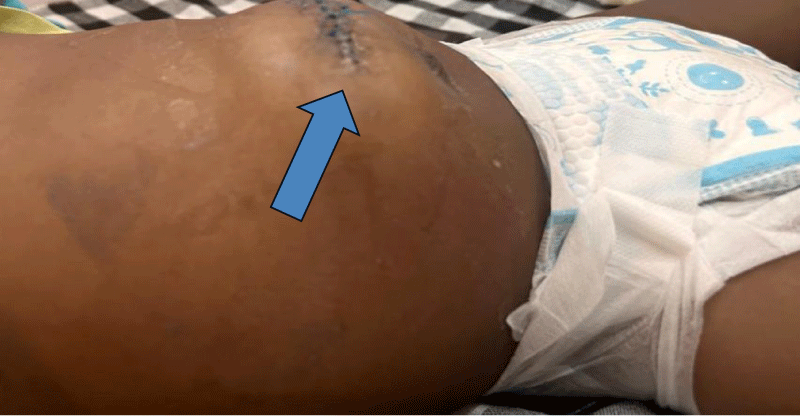

Despite these complications, the patient showed gradual improvement over the following week. The wound edges were approximated, but an incisional hernia was evidence, which would require further surgical intervention. The patient was discharged on the 22nd postoperative day for both pediatric and pediatric surgical follow-up (Figure 3).

Figure 3: Postoperative healing with incisional hernia (arrow).